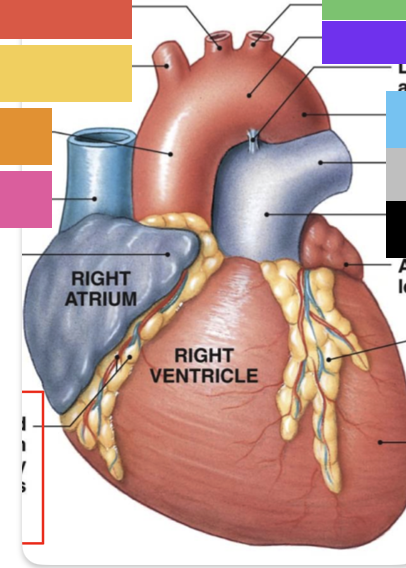

light purple

base

purple

apex

grey

right atrium

pink

right auricle

green

left atrium

green

left auricle

blue

right ventricle

orange

left ventricle

pulmonary trunk

ascending aorta

aortic arch